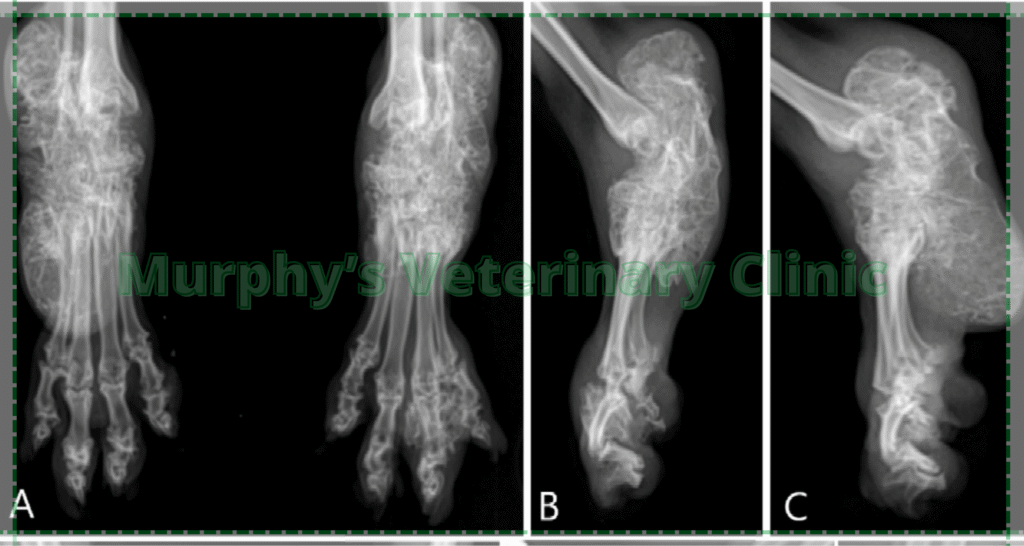

Hypervitaminosis A, caused by excessive vitamin A intake, can result in serious bone and joint issues in pets, especially young cats. It disrupts bone metabolism, leading to abnormal bone growth, stiffness, reduced mobility, and chronic pain. In kittens, it may cause permanent deformities if untreated. A common cause is overfeeding vitamin A–rich foods like liver. Many owners mistakenly consider liver a healthy treat, unaware of its toxicity risk. Preventing this condition requires balanced nutrition and limiting high–vitamin A foods.

Key Risks

- Dietary excess – frequent or large amounts of vitamin A–rich foods.

- Bone growth disruption – causes deformities and stiffness.

- Vulnerability in young cats – higher risk of permanent damage.

- Chronic discomfort – long-term pain from skeletal changes.